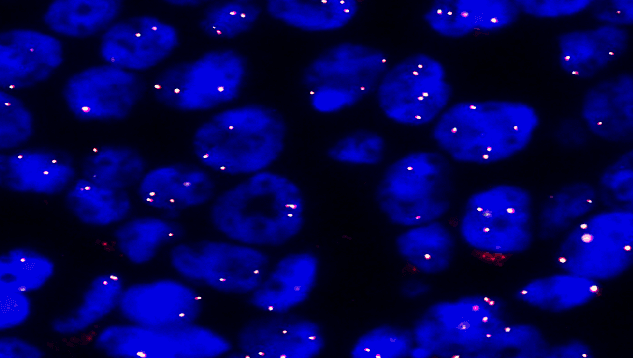

Human ALK gene fusion detection probe

ALK dual color probe

ALK gene 5’ end labeled as green, with a length of 700 kb; ALK gene 3’ end labeled as orange, with a length of 300 kb.